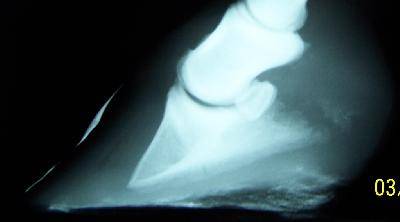

При рентгенографии скакательного сустава, как правило, тоже используют две стандартные проекции, но этот сустав сложный по строению и состоит из нескольких рядов косточек, и они-то точно накладываются друг на друга. А при выполнении дорсомедиально-плантаролатеральной проекции становятся видны те участки, в которых можно было бы легко пропустить наличие околосуставных остеофитов. В предпродажный осмотр теперь все чаще стали включать рентгеновское обследование коленного сустава, так как в этой области нередко бывает расслаивающийся остеохондроз и подхрящевые кистоподобные повреждения.

Рентгеновское изображение дает информацию об изменениях в плотности ткани, форме, размере, контурах и положении, главным образом, костей и суставов. Но современная цифровая радиография позволяет дать информацию и о состоянии мягких тканей, сосудов (контрастная рентгенография), связок и сухожилий.

Радиография – важная часть в диагностической оценке хромающей лошади и при ее предпродажном осмотре.